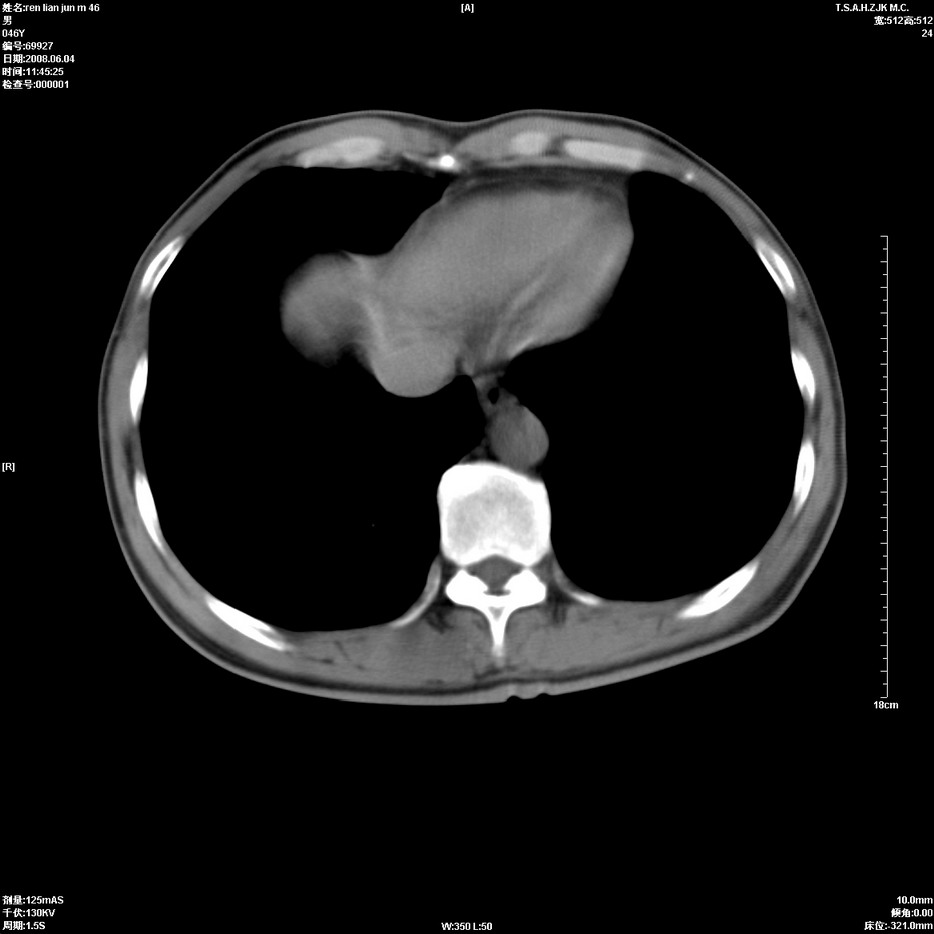

以下是引用qiu999在2008-6-5 17:14:00的发言:[br]考虑右肺中心型肺癌.颅内应做增强检查.

以下是引用形影不离在2008-6-5 19:18:00的发言:[br]右肺中心型肺癌并纵隔及左侧腋窝淋巴结转移,颅内应做增强检查。

以下是引用杀毒软件在2008-6-5 18:33:00的发言:[br]支持考虑右肺中心型肺癌,颅内病变是不是转移,不好说